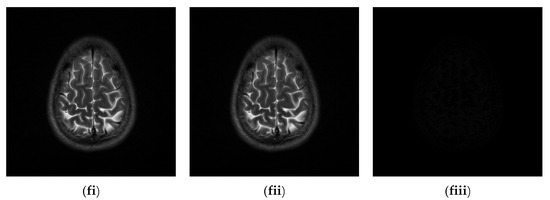

Figure 10.

Six medical test images; (a) Brain CT scan image (i); (b) Brain CT scan image (ii); (c) Thorax X-ray image (i); (d) Thorax X-ray image (ii); (e) Brain MRI scan image (i); (f) Brain MRI scan image (ii).

4.2. Experimental Results for Medical Images

Since the interpolation-based RDH schemes are designed for the special purpose of embedding patient information into medical images, the performance of our proposed adaptive RDH scheme on medical images is the main concern. Figure 11 shows the original image and its corresponding confidential image with 2 bpp secret data embedded, and images showing the difference between the original medical images and their confidential images. The difference images (aiii–fiii) in Figure 11 show almost nothing, which indicates that the proposed scheme does not look much different from the original image after hiding and will not draw the eavesdropper’s attention.

Figure 11.

The original images, the confidential images, and the different images; (ai–fi) The cover images; (aii–fii) The confidential images; (aiii–fiii) The difference between the cover images and the confidential images.